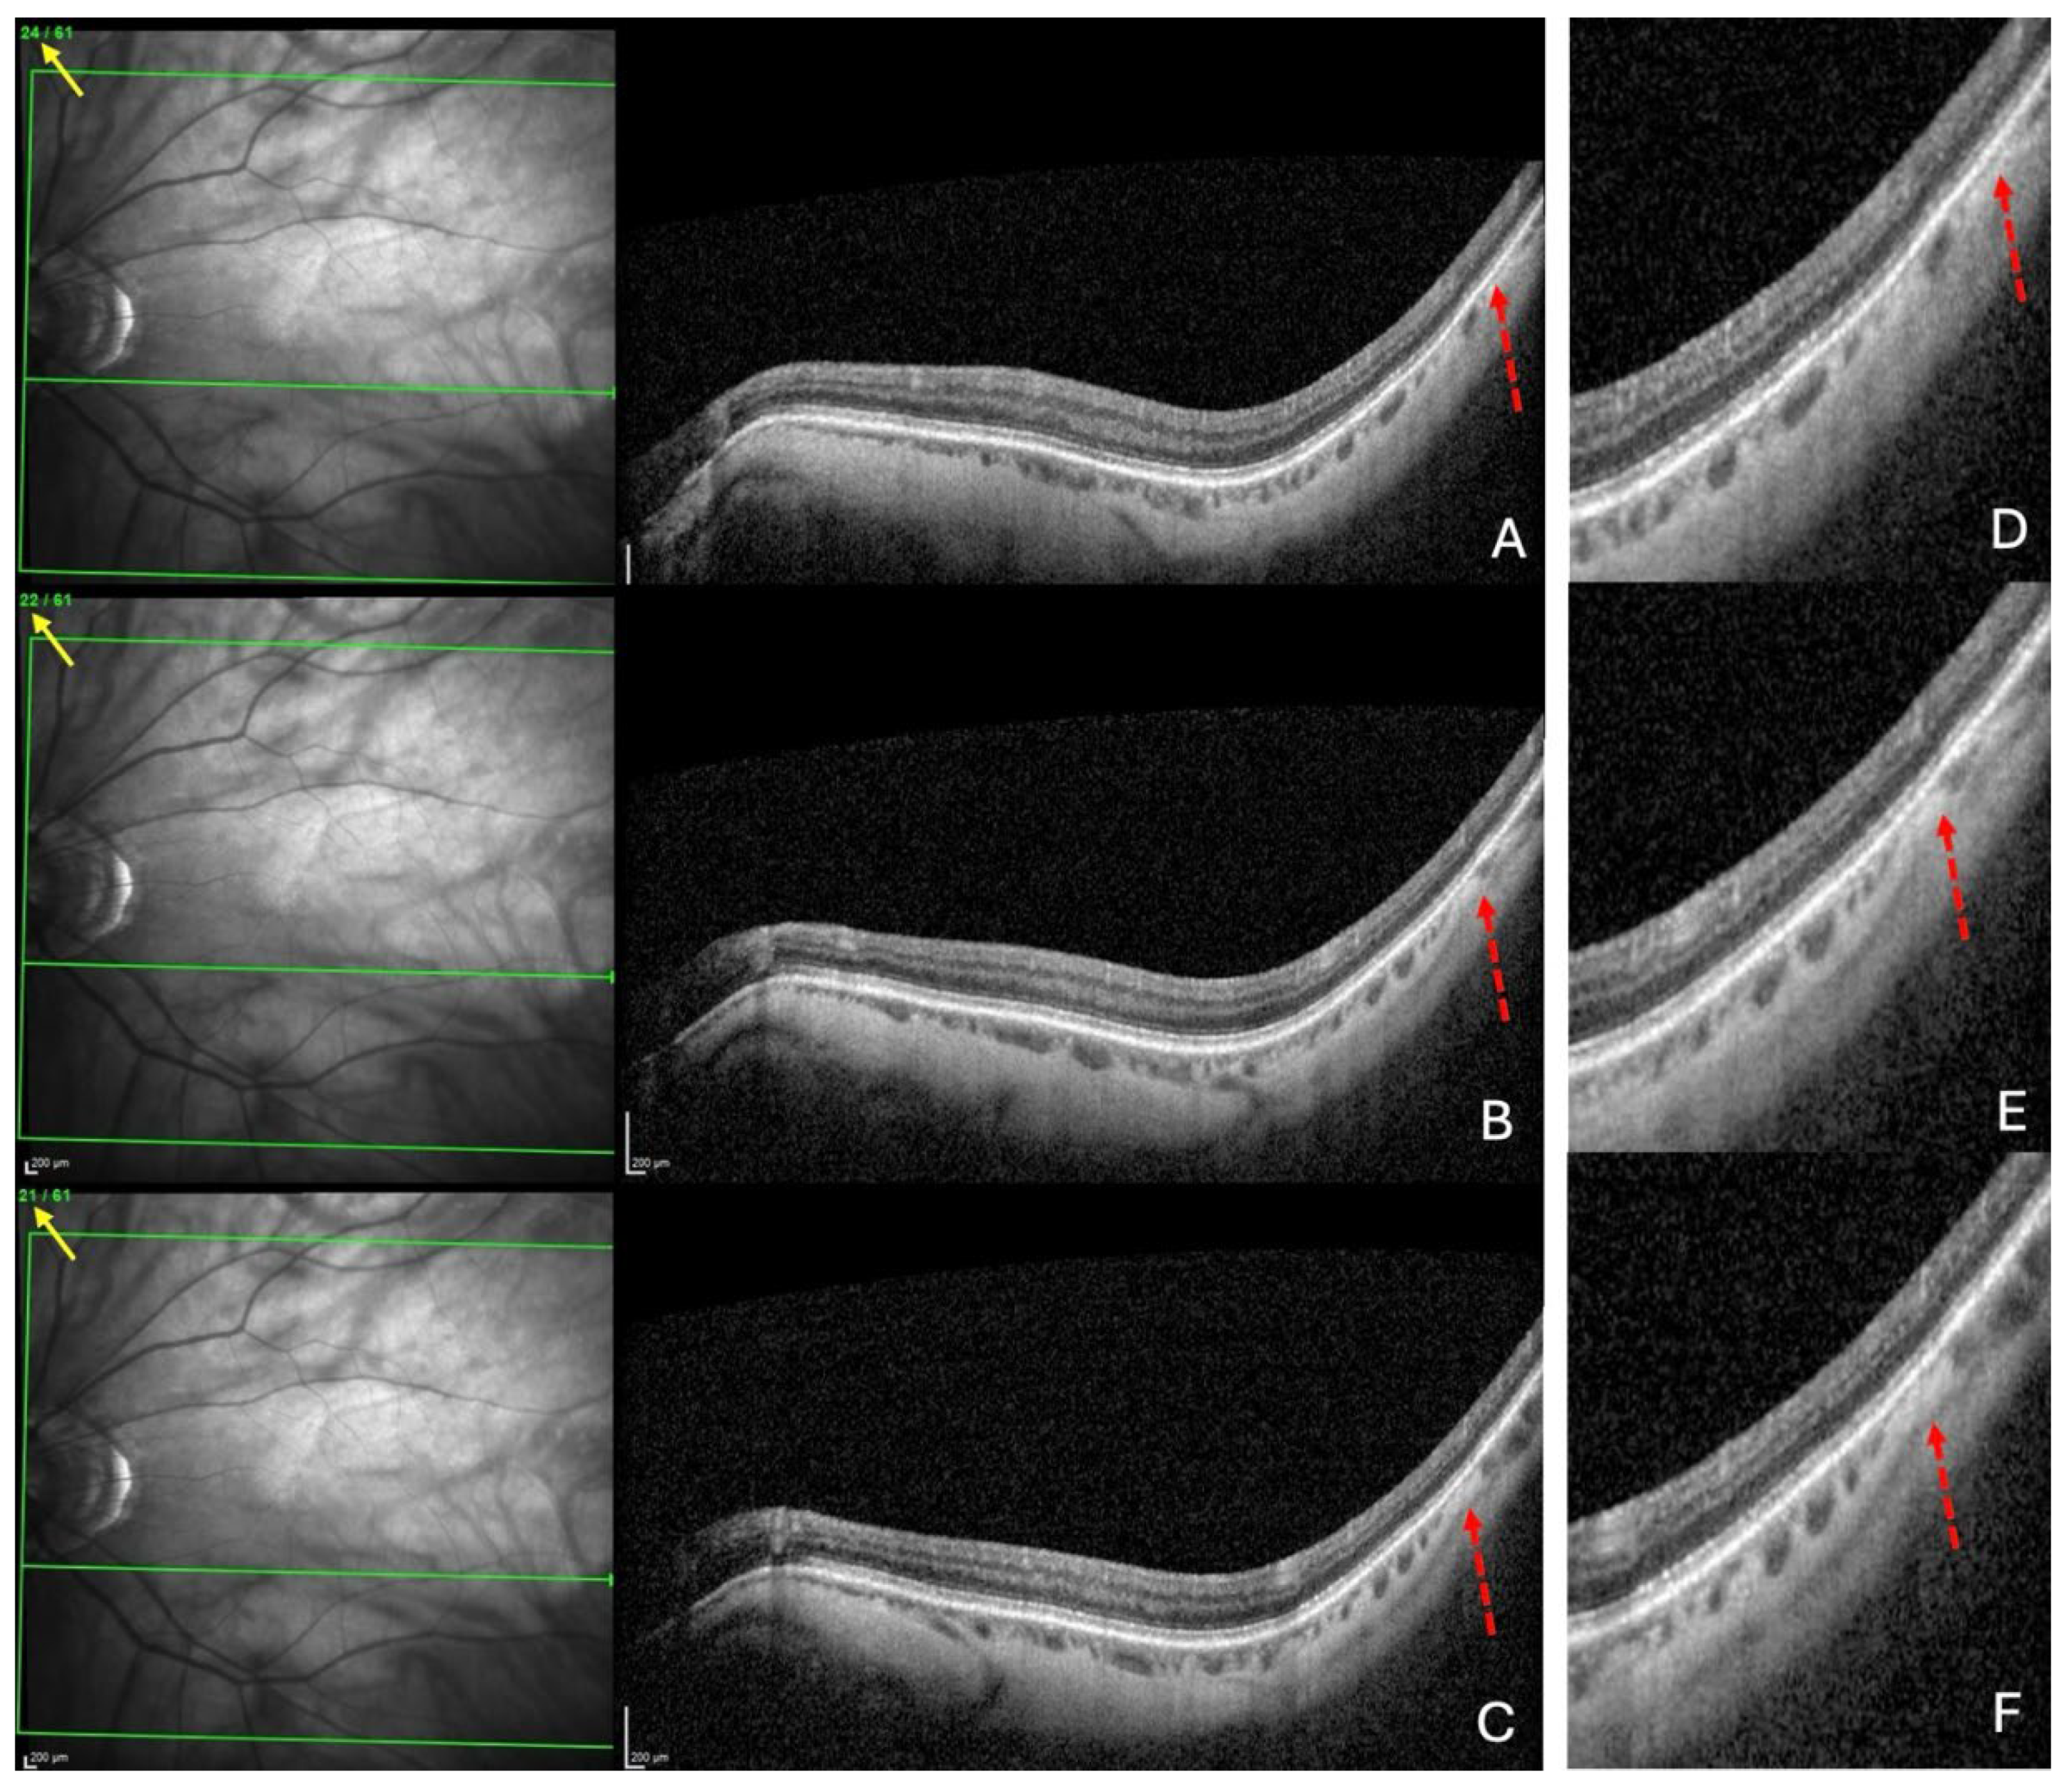

2.1.2. OCT Analysis.

- Search for choroidal thinning in 3 locations in the temporal part of the posterior pole.

- Measurement of the choroidal thinning and distance from fovea to thinning.

3.4. Detailed Analysis of Choroidal Thinning at the Vicinity of the Fo-BMO Axis (ChT)

3.5. Analysis of the Distance ChT – Fovea (FT-Distance)